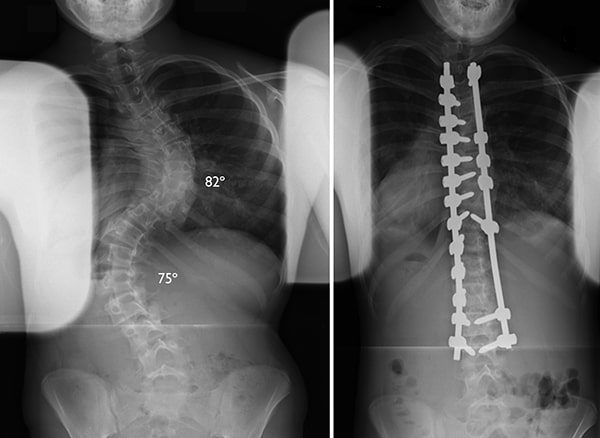

X-rays of a scoliosis curve before and after spinal fusion

(Left) This X-ray shows two large curves that require surgery. (Right) The same patient after surgery to correct the curves.

Courtesy of Texas Scottish Rite Hospital for Children